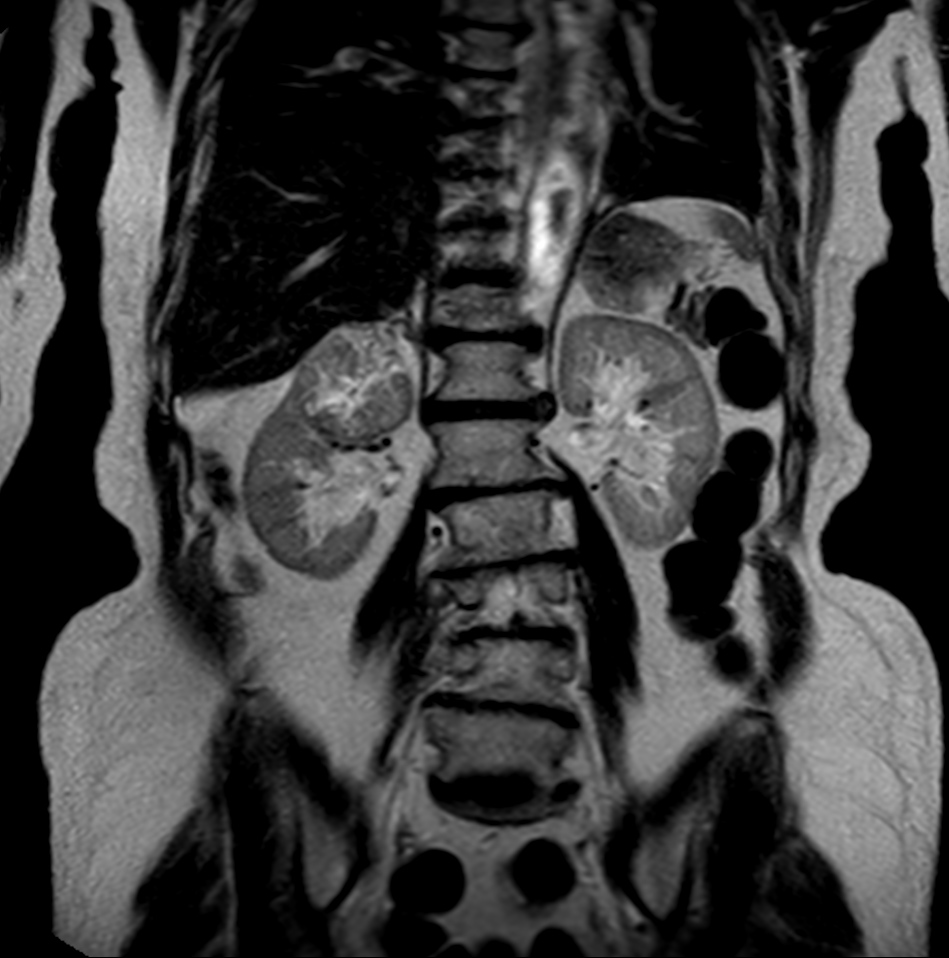

Patient with a kidney lesion. The ExamCard includes techniques for 3D imaging (PelvisVIEW, eTHRIVE) allowing for multiple image directions in one single scan, efficient fat-free imaging over large field-of-views (mDIXON XD), a multi-phase contrast-enhanced sequence (4D FreeBreathing) to improve imaging confidence and Compressed SENSE to accelerate the entire exam.

T2w TSE heavy weighted

T2w TSE FatSat MultiVane XD

T2w TSE